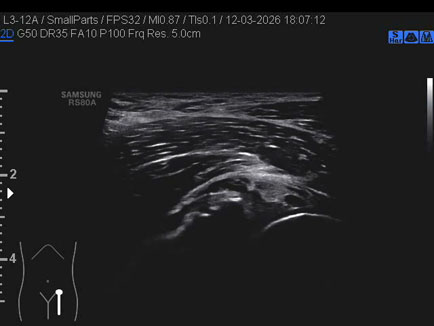

Data inserimento: 23/03/2026

Ecografia del: 12/03/2026

Strumento: Samsung

Sonda: Lineare

Commento all'esame: ganglio del cercine cotiloideo.

Conclusioni: ganglio del cercine cotiloideo (ganglion of the cotyloid labrum).

Realizzazione: Dr. F. Pietro Tarini - Gubbio (PG)

Presentazione: Dr. Massimo Dolciotti - Ancona